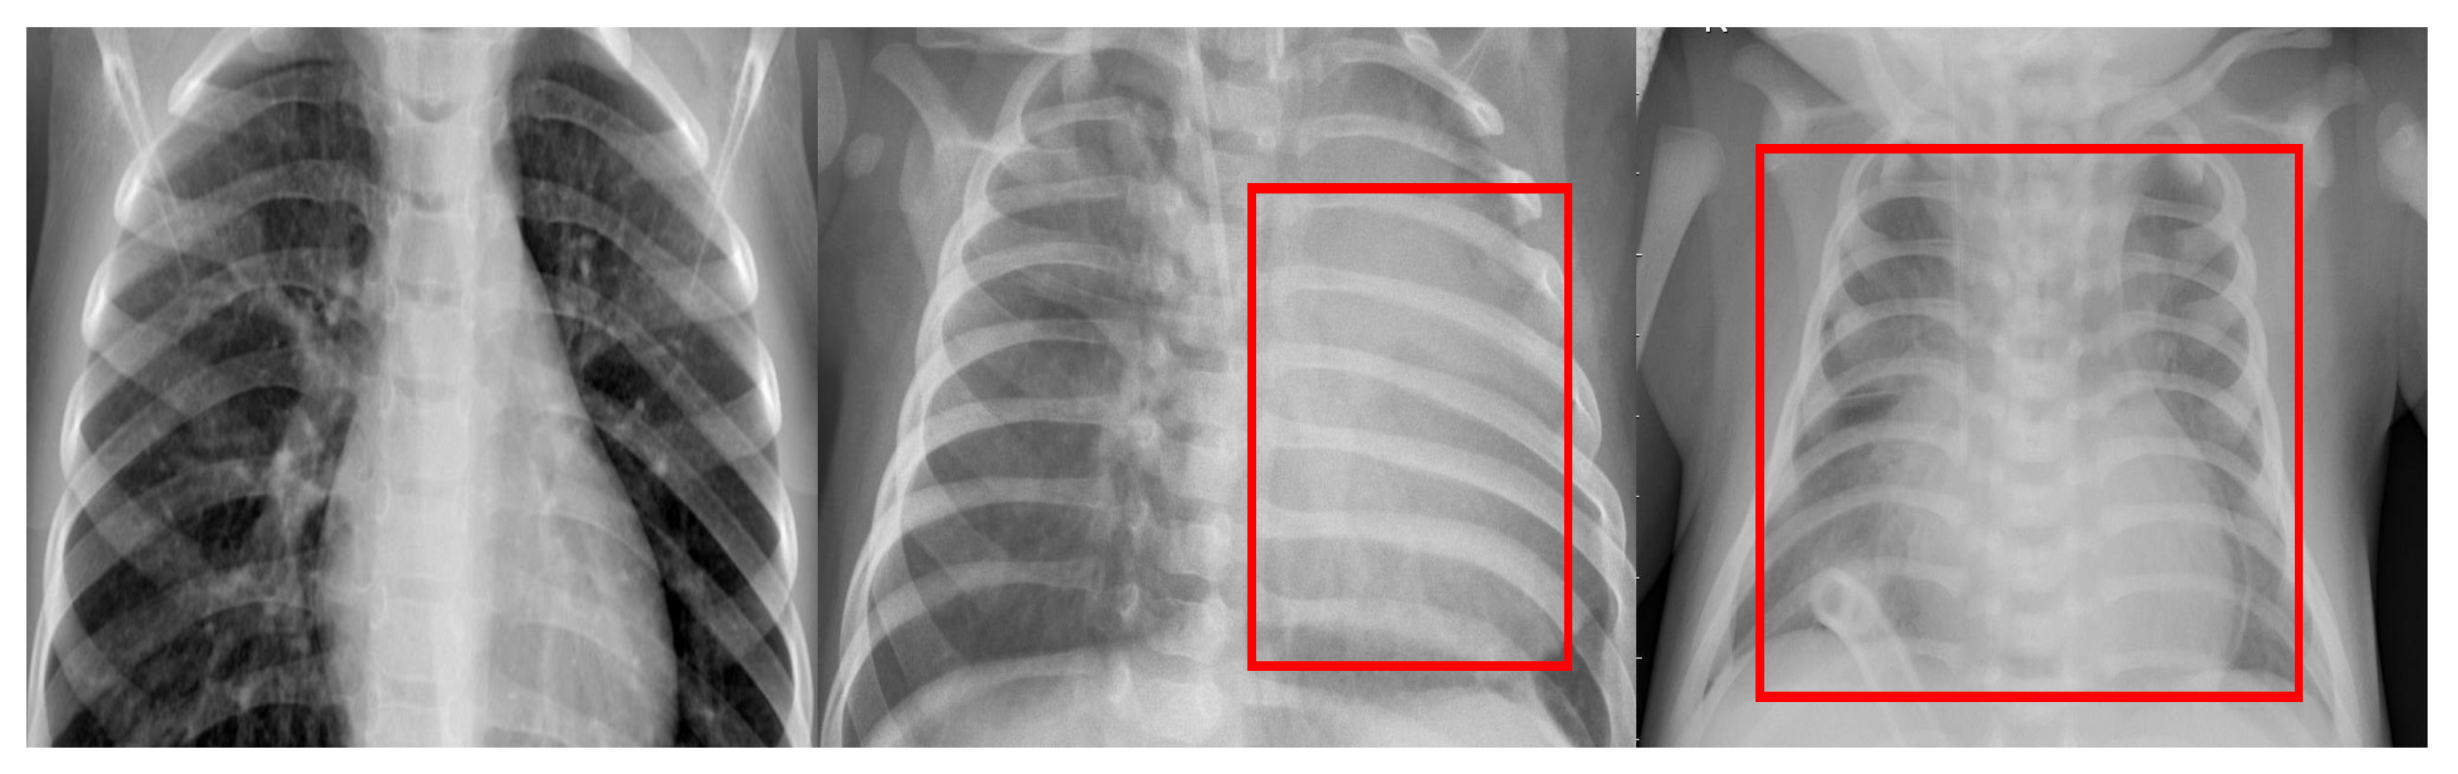

1.1. Related Work

3.2. Normal vs. Bacterial vs. Viral Pneumonia Infected Lungs